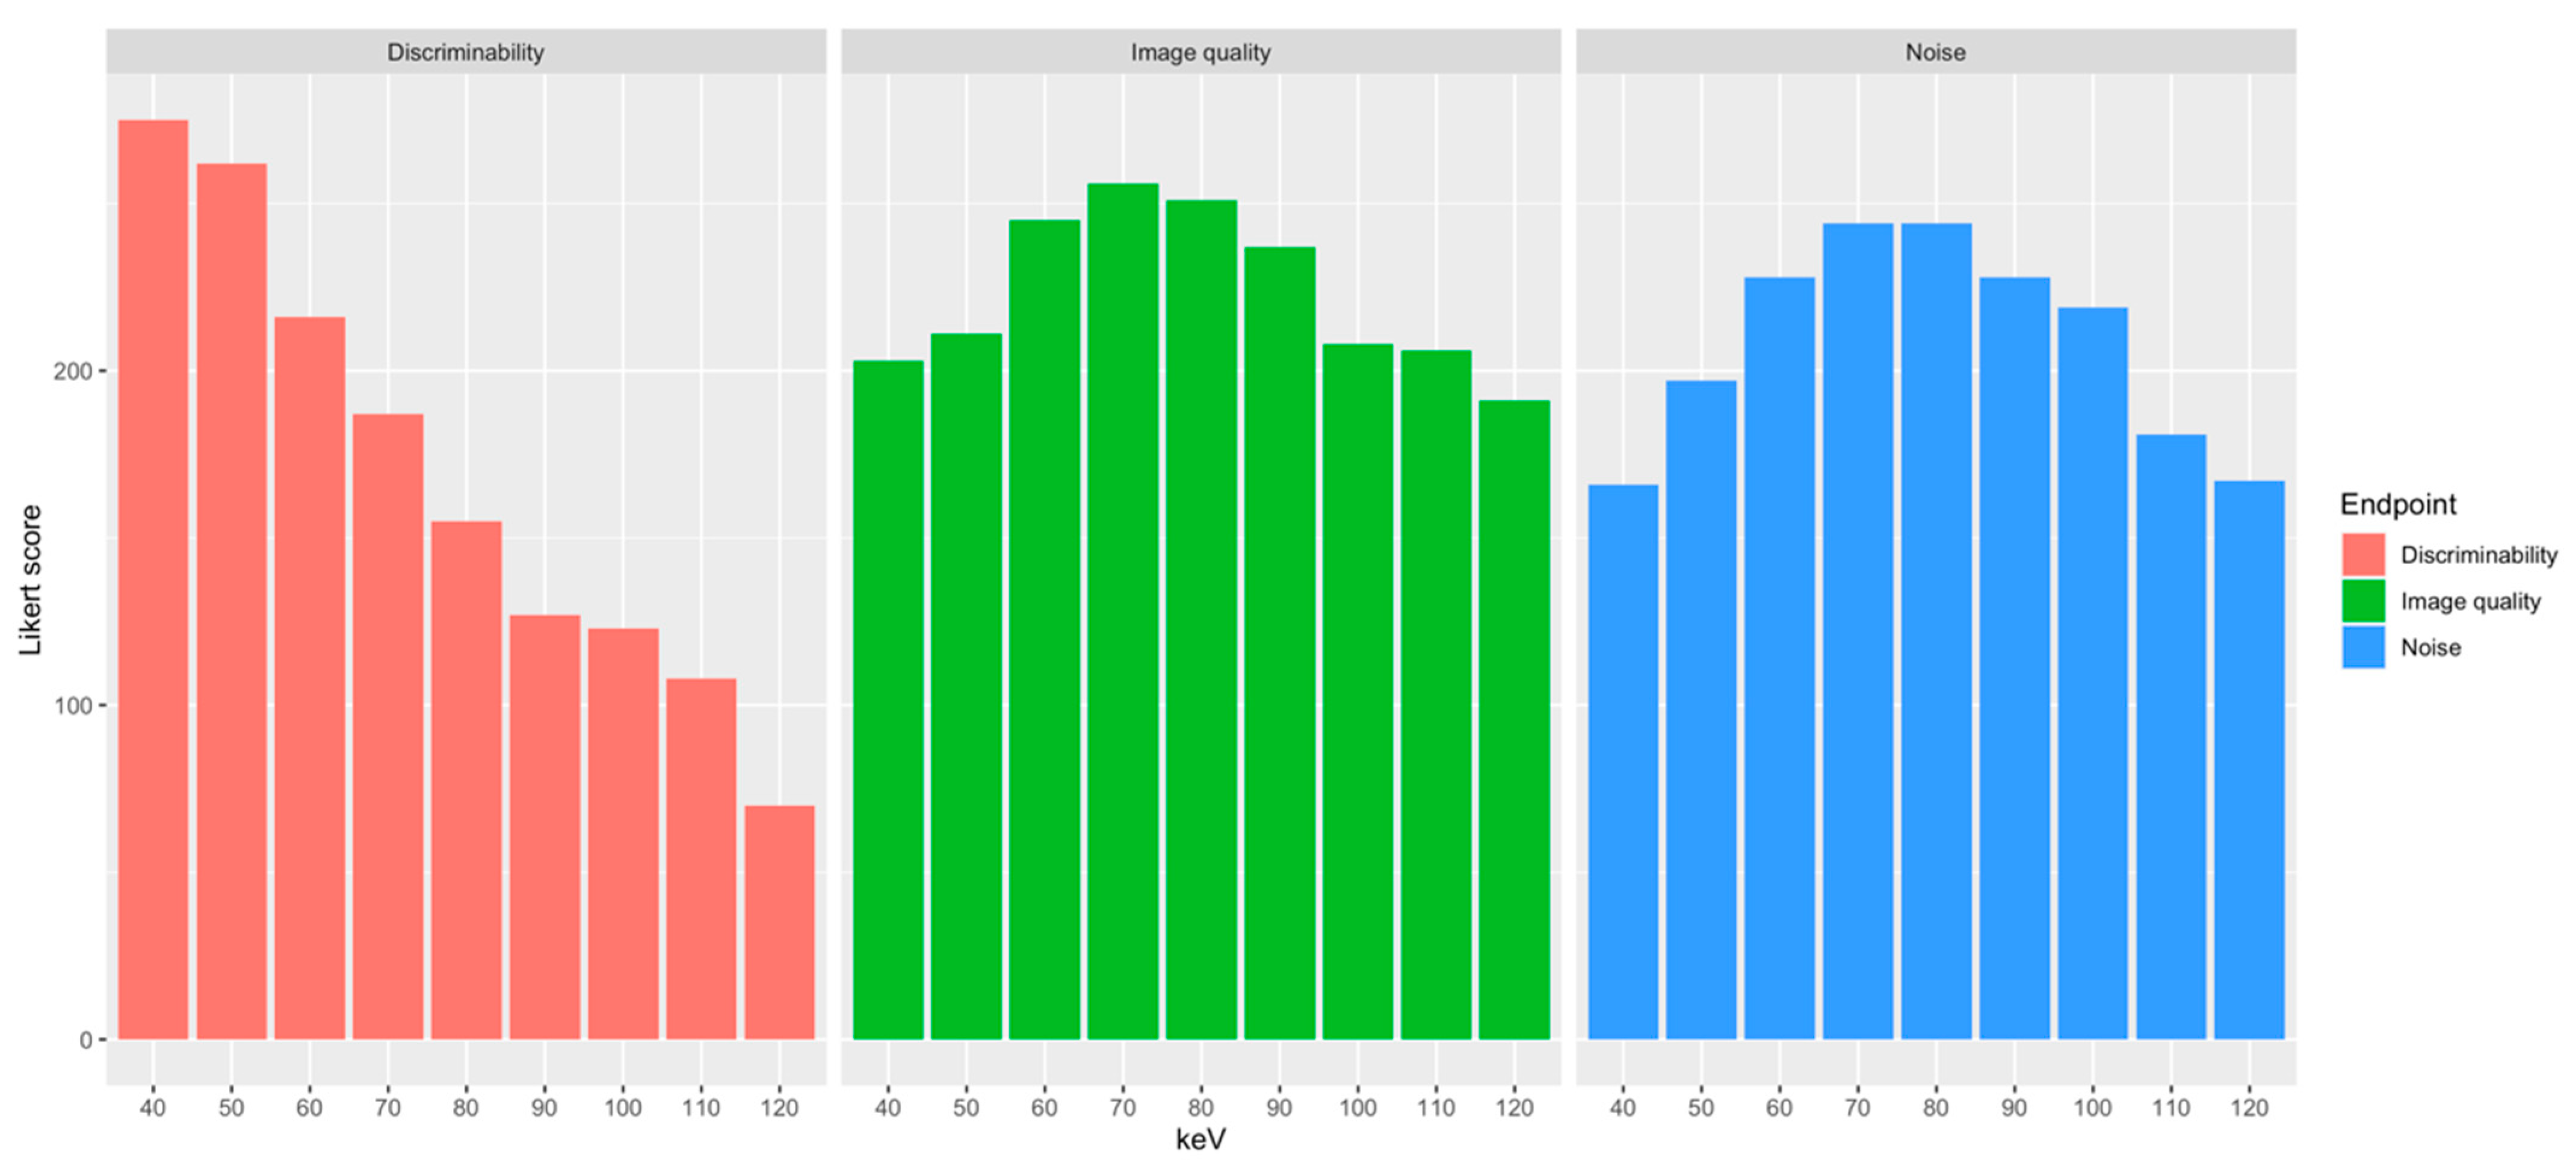

3.3. Qualitative Image Analysis

| Energy Level | Discriminability | Noise | Image Quality | Overall Score |

| 40 keV | 4.66 ± 0.69 | 2.81 ± 0.6 | 3.44 ± 0.6 | 644 |

| 50 keV | 4.44 ± 0.56 | 3.34 ± 0.61 | 3.58 ± 0.53 | 670 |

| 60 keV | 3.66 ± 0.69 | 3.86 ± 0.47 | 4.15 ± 0.48 | 689 |

| 70 keV | 3.17 ± 0.77 | 4.14 ± 0.39 | 4.34 ± 0.48 | 687 |

| 80 keV | 2.63 ± 0.79 | 4.14 ± 0.47 | 4.25 ± 0.51 | 650 |

| 90 keV | 2.15 ± 0.66 | 3.86 ± 0.73 | 4.02 ± 0.68 | 592 |

| 100 keV | 2.08 ± 0.92 | 3.71 ± 0.85 | 3.53 ± 0.8 | 550 |

| 110 keV | 1.83 ± 0.91 | 3.07 ± 1.27 | 3.49 ± 0.8 | 495 |

| 120 keV | 1.18 ± 0.43 | 2.83 ± 1.29 | 3.24 ± 0.82 | 428 |